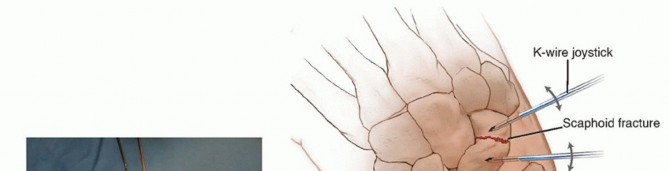

Illustration of volar to dorsal - Dr. Mohammed Hutaif

TECH FIG 2 • A-C. Before screw insertion, the position of the Kirschner wire must be changed from its position used for arthroscopy. The Kirschner wire should be driven from volar to dorsal until the distal end lies just beneath the articular surface of the scaphoid. D,E. Screw fixation of minimally displaced scaphoid fracture via the dorsal percutaneous technique. The screw tip should rest within 1 to 2 mm of the distal cortex. Excellent compression should be obtained with this technique.

TECH FIG 3 • A. Reduction of a displaced scaphoid waist fracture using Kirschner wire joysticks. B. The Kirschner wire joystick technique for fracture reduction.(continued)

TECH FIG 3 •(continued)C. The guidewire is pulled volarly until it remains only in the distal fragment. The joysticks are then utilized to reduce the fracture. D. The guidewire is driven from volar to dorsal, transfixing the proximal fragment.